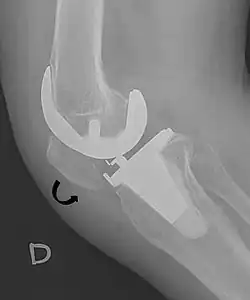

5. ^ Melloni, Pietro; Veintemillas, Maite; Marin, Anna; Valls, Rafael (2013). "Imaging Patellar Complications After Knee Arthroplasty". Arthroplasty - Update. doi:10.5772/53666. ISBN 978-953-51-0995-2. (CC-BY-3.0)